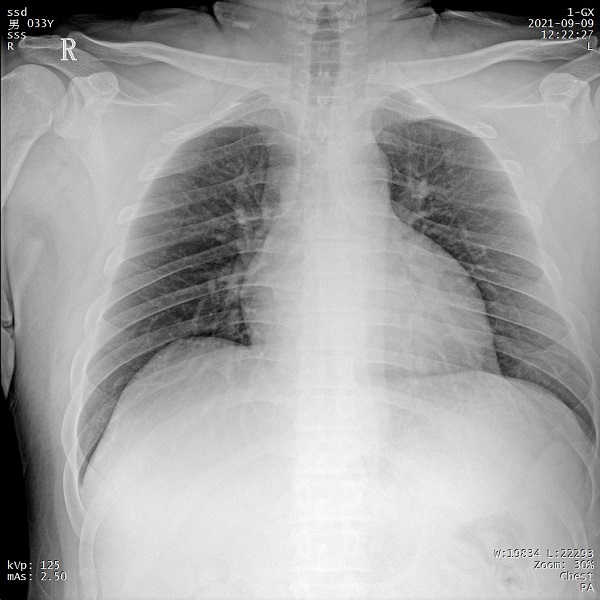

一、肥胖患者、組織較厚部位清晰成像

管電流大小與設(shè)備輸出X射線的能力相關(guān),管電流越大,設(shè)備輸出的射線量越充沛。PLX5500的管電流達(dá)到了710mA,輸出的射線能夠滿足各體型患者的拍攝需求,即便是體重達(dá)上百公斤的患者,也能夠獲得清晰的圖像。

二、1ms 短時曝光 定格心肺運動瞬間影像

PLX5500系列移動DR能夠在1ms的曝光時間內(nèi)輸出足量的X射線,獲取清晰圖像。特別適用于拍攝肺炎、塵肺病、肺結(jié)核等難以憋氣的患者,避免了因患者肺部呼吸運動而產(chǎn)生的運動偽影的影響,瞬間定格清晰圖像,以供醫(yī)生準(zhǔn)確診斷。

三、支持高千伏攝影 肺部紋理更有層次

PLX5500系列移動DR的可調(diào)千伏達(dá)到150kV,在達(dá)到一定高電壓后,與骨骼相重疊的軟組織或骨骼本身的細(xì)小結(jié)構(gòu)及含氣的管腔等,均可清晰顯示。